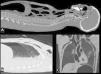

In the chest region, we noted subcutaneous emphysema around the external injuries, and 2 regions had greater extension into the subcutaneous tissue of the thoracic region (left lateral and axillary area and the anterior thoracic region, Figure1).

PMCT images, sagittal multiplanar reconstruction (A and B) and coronal (C) pulmonary window settings. The following structures are labeled with arrows pointing to the gas contents: A) dural venous plexus, central vein of the vertebral body of C6 and other veins in the cervical vertebral bodies (note the dense liquid inside the trachea); B) subcutaneous emphysema in the soft tissues of the right anterior thorax; C) and more extensive subcutaneous emphysema in the left lateral aspect of the thorax.